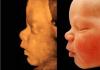

@amina_mmmm, ой, не знаю

Я все узи делала у Тамары Салиховны🫶🏻

Скорее это 4D

@ahmedova3, одно лицо 🤣

@ahmedova3, я не думала, что настолько похож будет